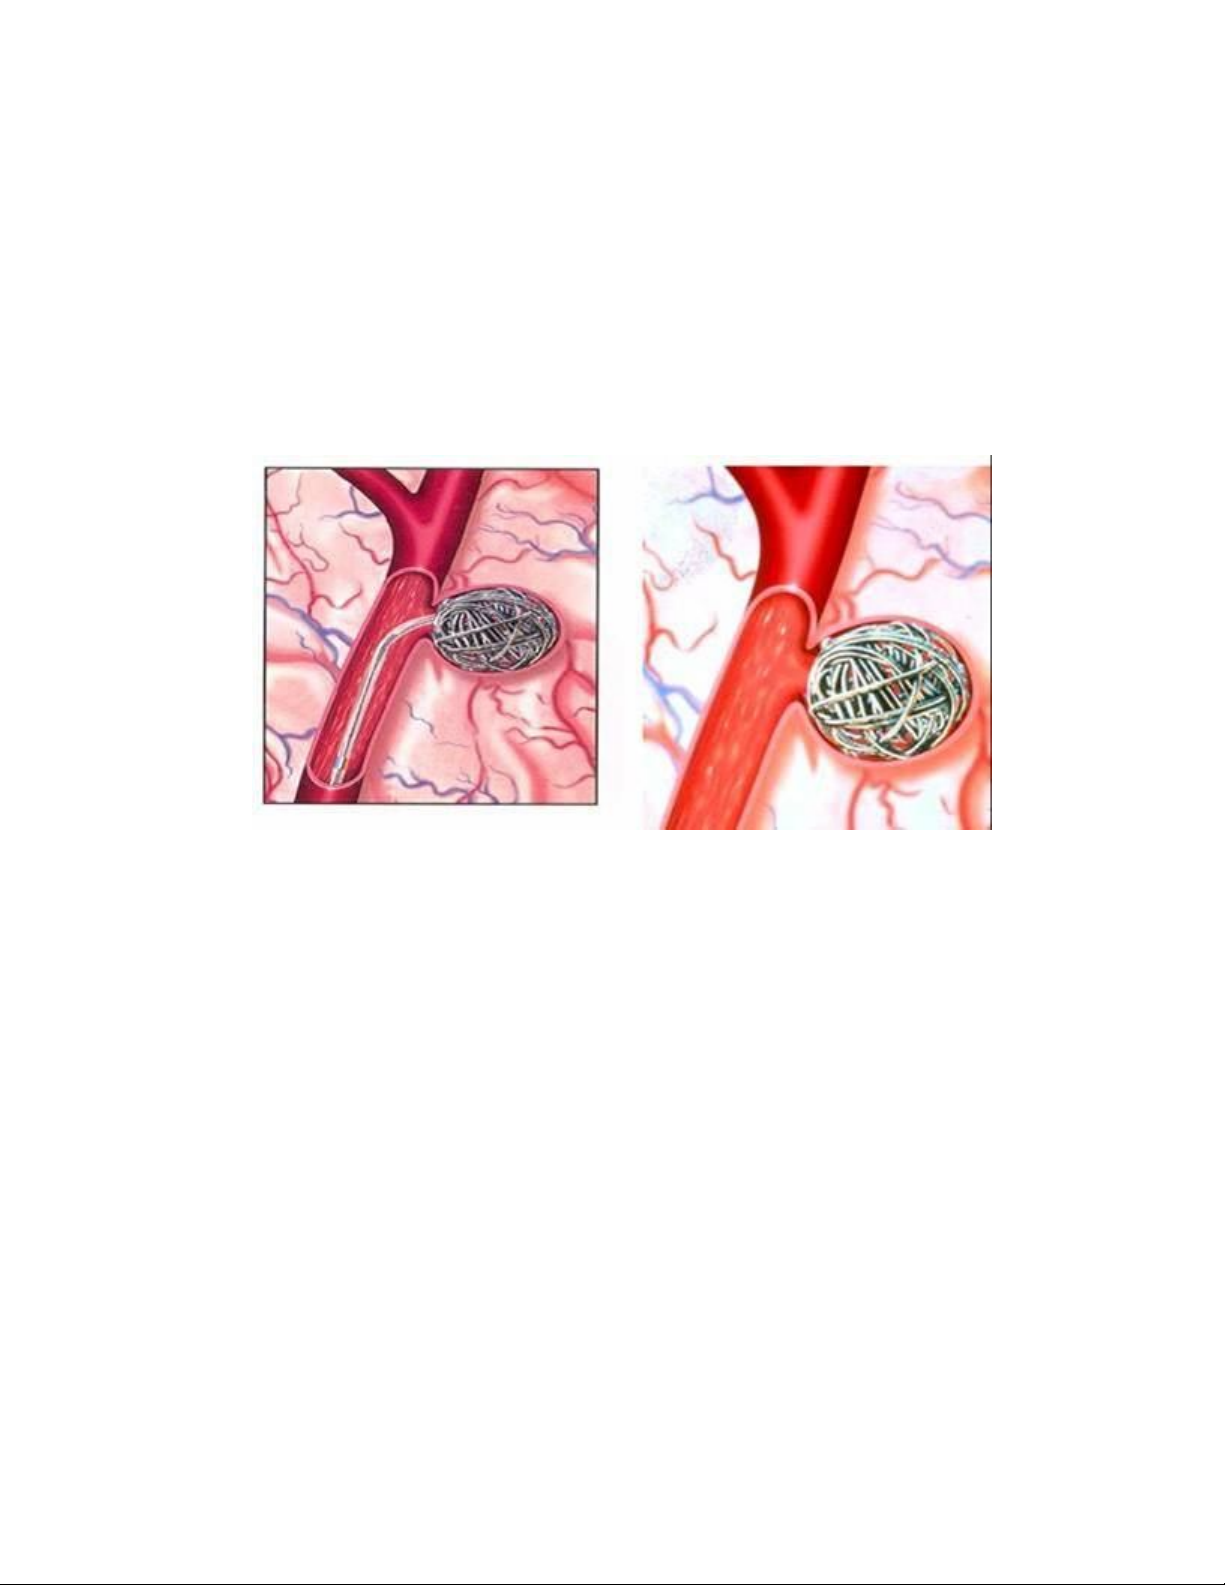

b. Đặt giá đỡ hình vòng xoắn và bít túi phình (coiling): Bác sĩ X Quang

can thiệp sau khi đã xác định vị trí của túi phình bằng chụp mạch máu cản quang

sẽ luồn một giá đỡ dạng vòng xoắn và sợi bằng platin hoặc latex vào vị trí túi

phình. Thủ thuật này sẽ ngăn chặn máu không tiếp tục chảy vào túi phình được

nữa.

Dùng Coil để bít túi phình động mạch não